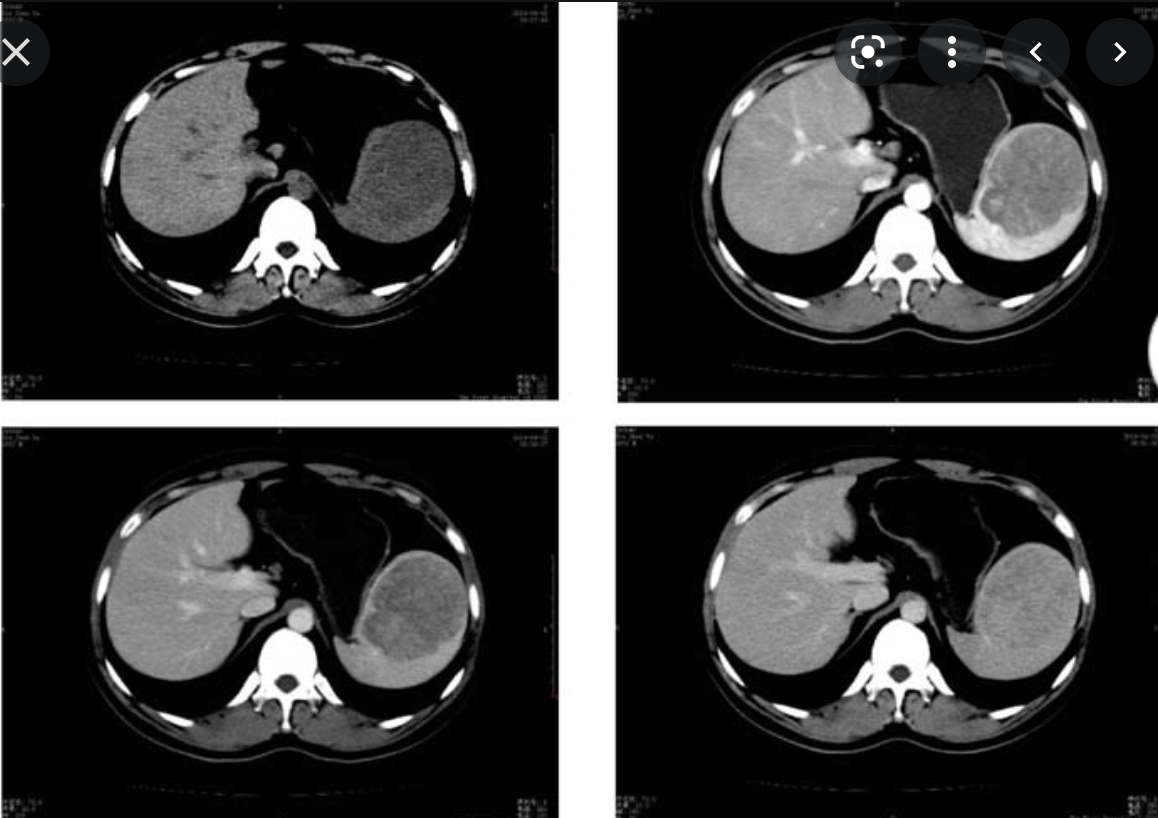

Annotated images showing the active contrast extravastation from the splenic hilum on both arterial and portal venous phases.

Case Discussion

The spleen is ‘shattered’ into pieces, with active contrast extravasation at the splenic hilum, which extends across the midline towards the hepatic hilum.

High attenuation fluid in the upper abdomen and pelvis in keeping with haemoperitoneum.

This is the highest grade splenic injury (grade 5).

The patient proceeded to an emergency splenectomy, which confirmed the above, including 1.5 litres of blood in the peritoneum, and a bleeding vessel at the splenic hilum.

The concomitant left renal laceration managed conservatively.